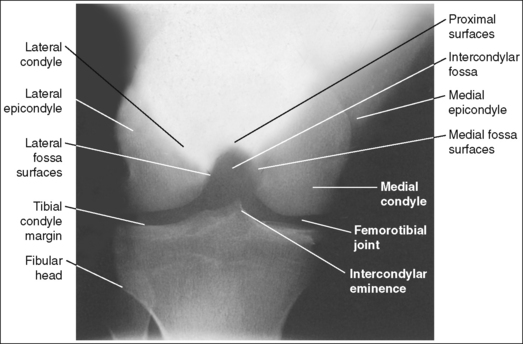

The medial and the lateral surfaces of the intercondylar fossa and the femoral epicondyles are in profile, and the fibular head is partially superimposed over the proximal tibia.

• The PA axial projection (Holmblad method) is performed by positioning the patient on hands and knees on the imaging table and then requesting the patient to lean forward until the femur and central ray form a 20- to 30-degree angle (femur–imaging table angle is 60 to 70 degrees; Figures 6-92 and 6-93). The IR is positioned under the affected knee.

The proximal surfaces of the intercondylar fossa are superimposed, and the patellar apex is demonstrated proximal to the intercondylar fossa.

• The proximal surfaces of the intercondylar fossa are superimposed when the femoral shaft is placed at a 60- to 70-degree angle with the imaging table (see Figure 6-92). To study this relationship better, place a femoral skeleton bone in the PA axial projection. While viewing the posterior intercondylar fossa, move the proximal femur closer to and farther away from the imaging table. Note how the proximal surfaces of the fossa are in profile and superimposed only when the femur is at a 60- to 70-degree angle with the imaging table. The position of the femur with respect to the imaging table also determines the position of the patella (see earlier AP knee projection discussion and Figure 6-74). As the knee is flexed (the proximal femur is brought away from the imaging table), the patella moves distally onto the patellar surface of the femur and into the intercondylar fossa. The degree of knee flexion used for the PA axial projection situates the patella just proximal to the fossa.